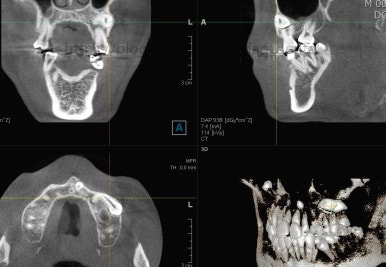

파노라마 X-ray 사진 입니다.

사랑니가 굉장히 위쪽으로 묻혀 있어요. 이렇게 묻혀 있는 사랑니는 사실상 그냥 놔둬도 괜찮아요.

과잉치가 보이네요. 앞니 사이에 과잉치는 굉장히 빈번한데 주위 치아에 안좋은 영향을 줄 때는 뽑는게 좋아요. 이번 환자분은 뽑기로 했어요.

입 안에서 보이지 않던 송곳니가 여기 있었네요. 송곳니는 굉장히 중요한 치아라서 왠만하면 살려 쓰는게 가장 좋긴한데요. 위치랑 다른치아와의 관계 등을 고려해서 뽑을지, 꺼내쓸 지를 결정해야 돼요.

송곳니 부위를 좀 더 정밀하게 CT 사진을 찍었어요.

매복치아를 꺼낼 수 있는 기능성, 주위치아가 오히려 손상 받지 않을지, 총 치료기간 등을 고려했을 때 이번에는 발치하기로 결정했어요.

돌출입을 개선할 때 일반적으로 작은 어금니를 발치교정 하는데, 이번의 경우 작은 어금니 대신 송곳니를 발치했다고 치면 되니까요.

매복치아를 꺼내서 쓸 수만 있다면 꺼내는게 가장 좋으나 이번의 경우는 아니였던 거지요.